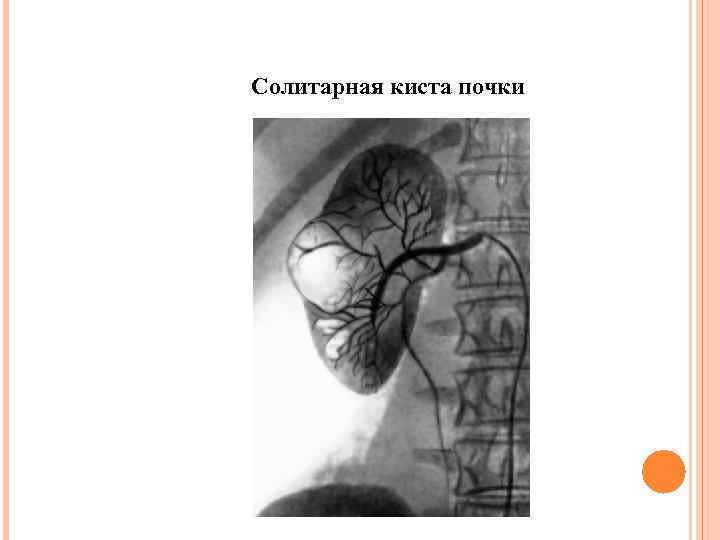

Солитарная киста почки

Солитарная киста почки